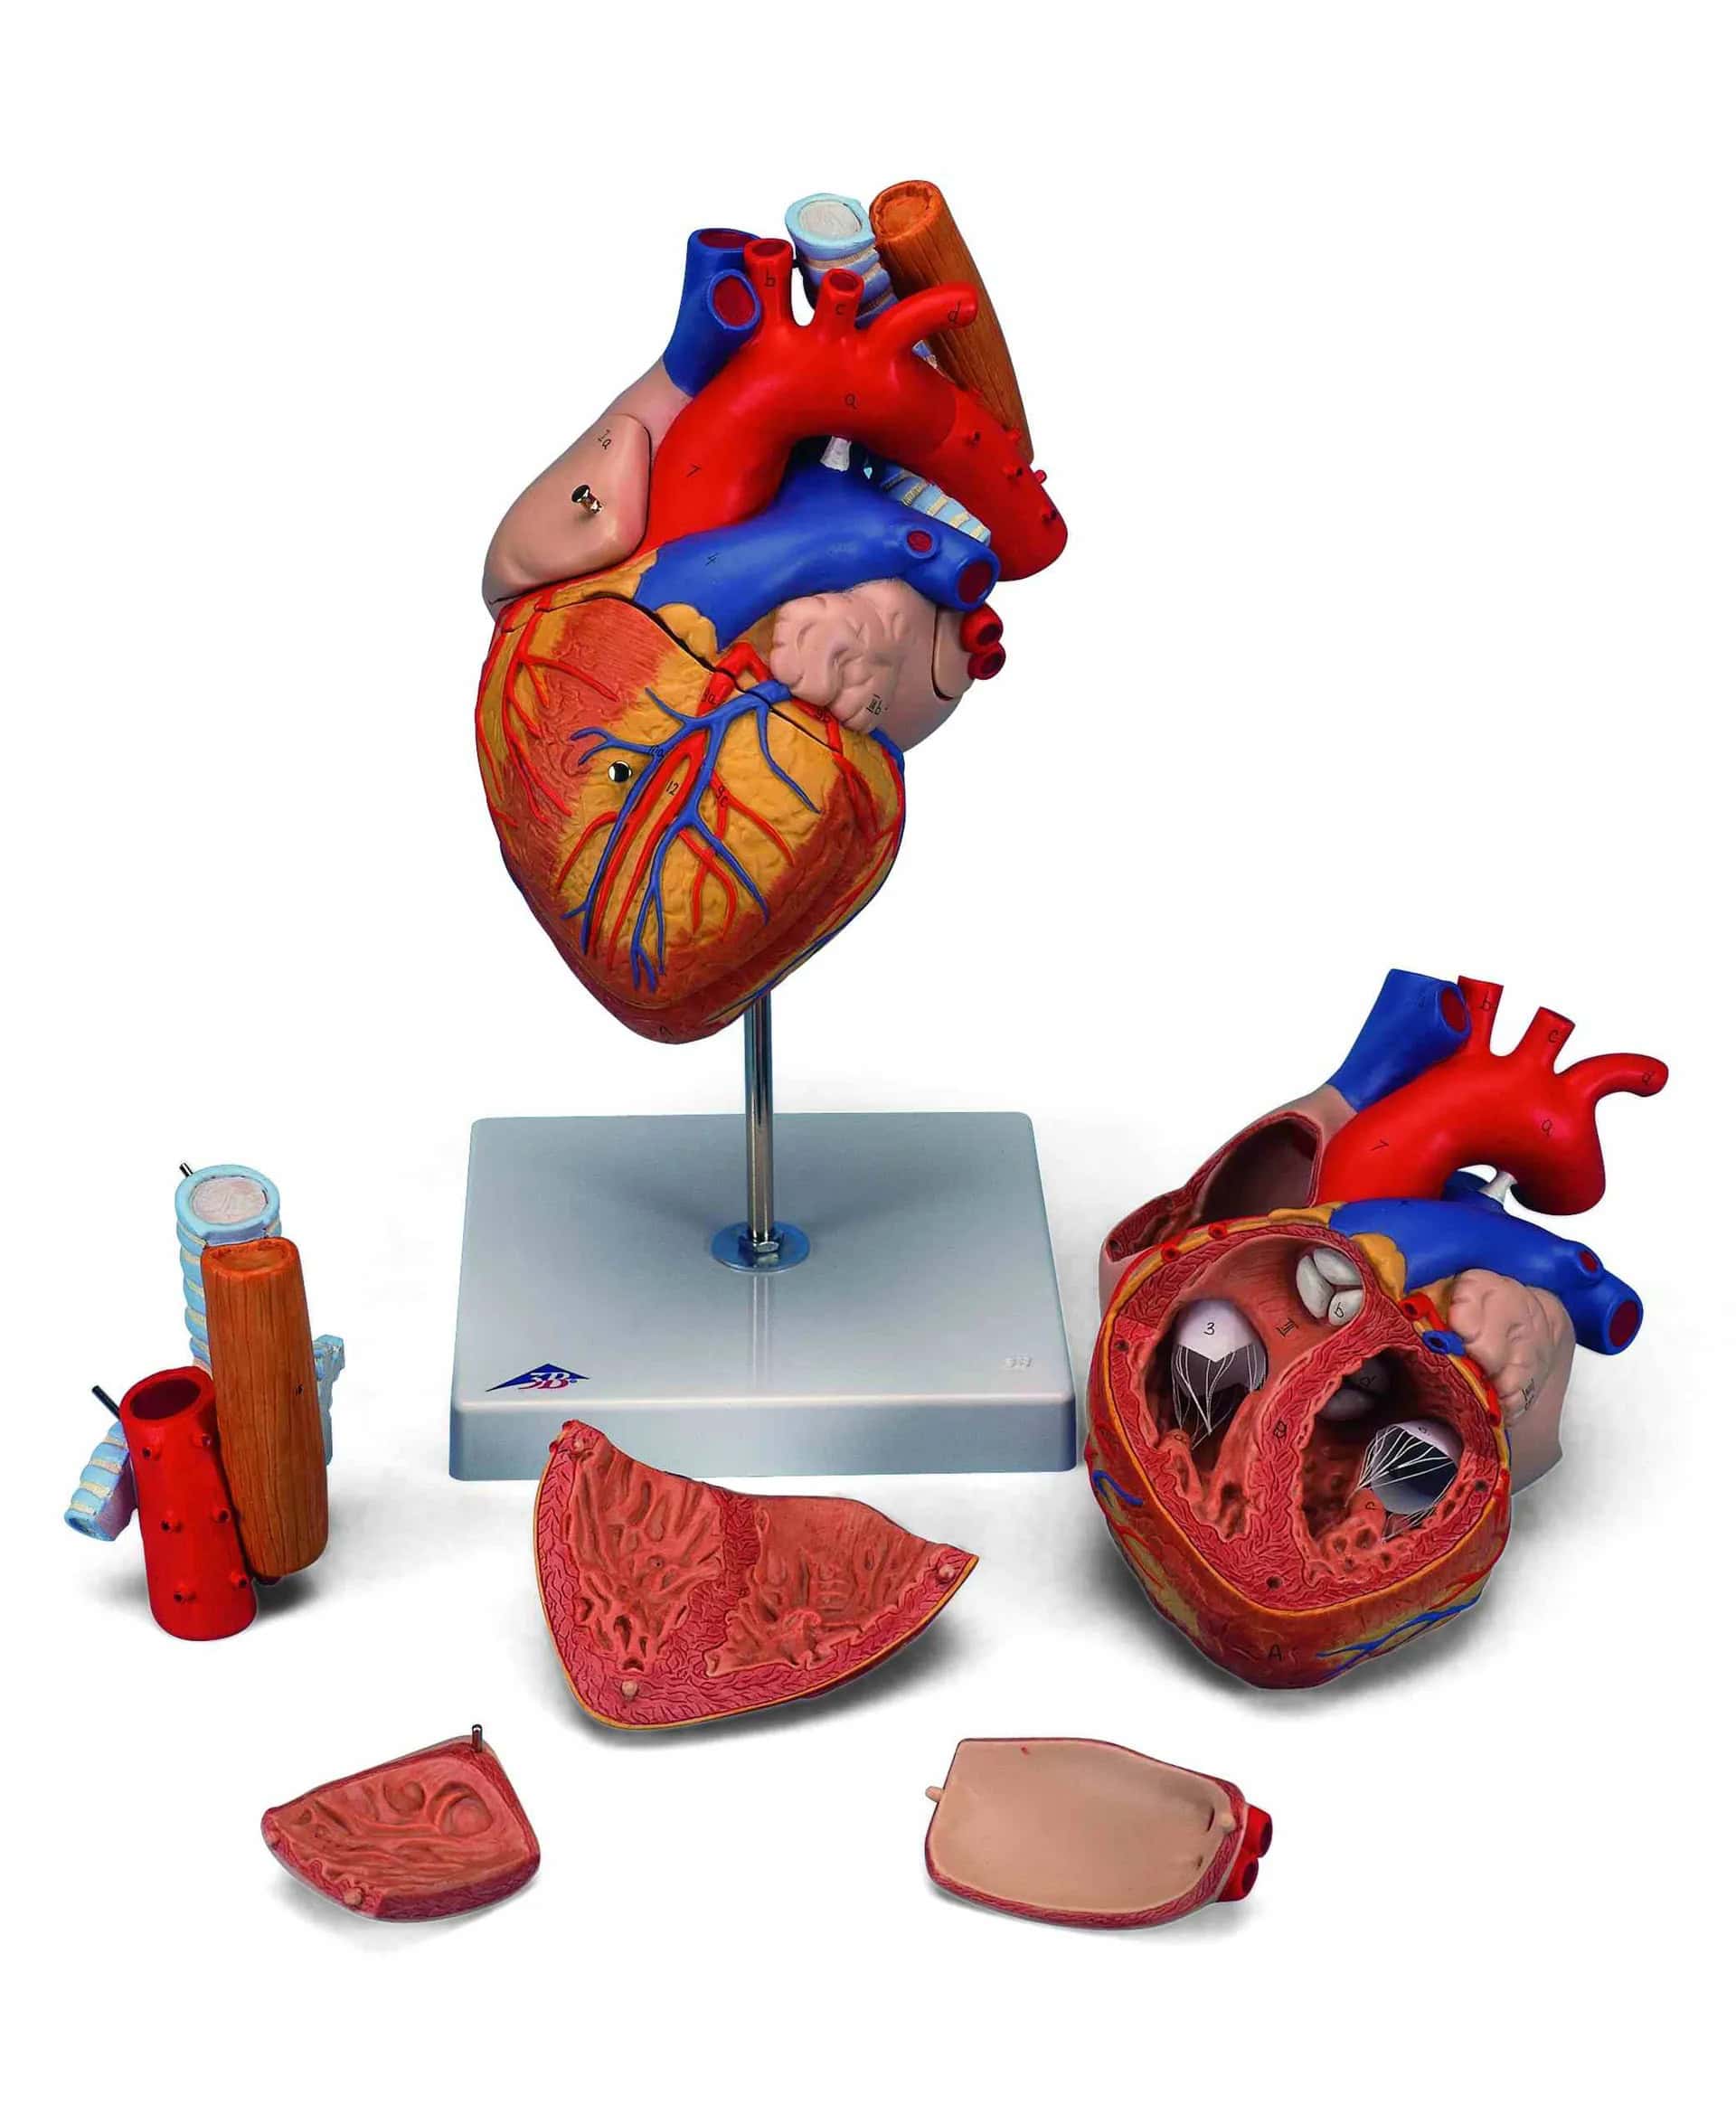

Torso tweeslachtig met open rug 28-delig